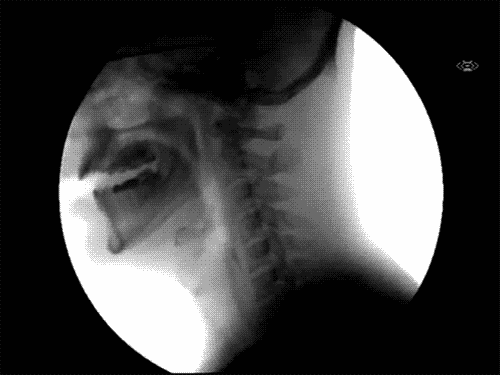

▼11. 在X光透视中,人类吞嚥的动作是这样的。